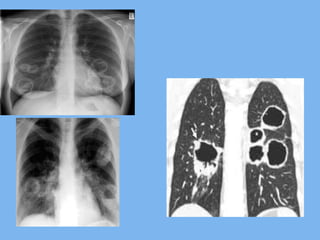

Wegener’s Granulomatosis

• Chronis sinusitis, Pulmonary nodules,

Pulmonary cavities, Rapidly Progressive

Glomerulonephritis

CT is the investigation of choice for

demonstrating lung lesions

Wegener’s Granulomatosis •Chronis sinusitis, Pulmonary nodules, Pulmonary cavities, Rapidly Progressive Glomerulonephritis • Cutaneous vasculitis, Eye lesions may be present • Non specific symptoms may predominate